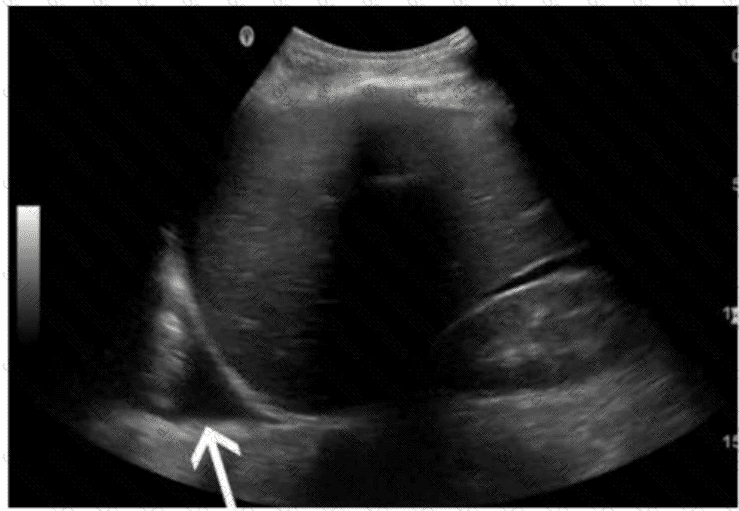

Which abnormality is depicted in this image of a patient who presents with a fever following a liver biopsy?